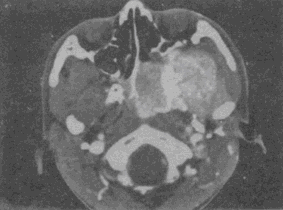

男,19岁,左侧鼻腔反复出血1年余,CT、MRI扫描如图,最可能的诊断是 YZ332_5_54_63.gif YZ332_5_54_63_1.gif YZ332_5_54_63_2.gif

• C.鼻咽部青年纤维血管瘤